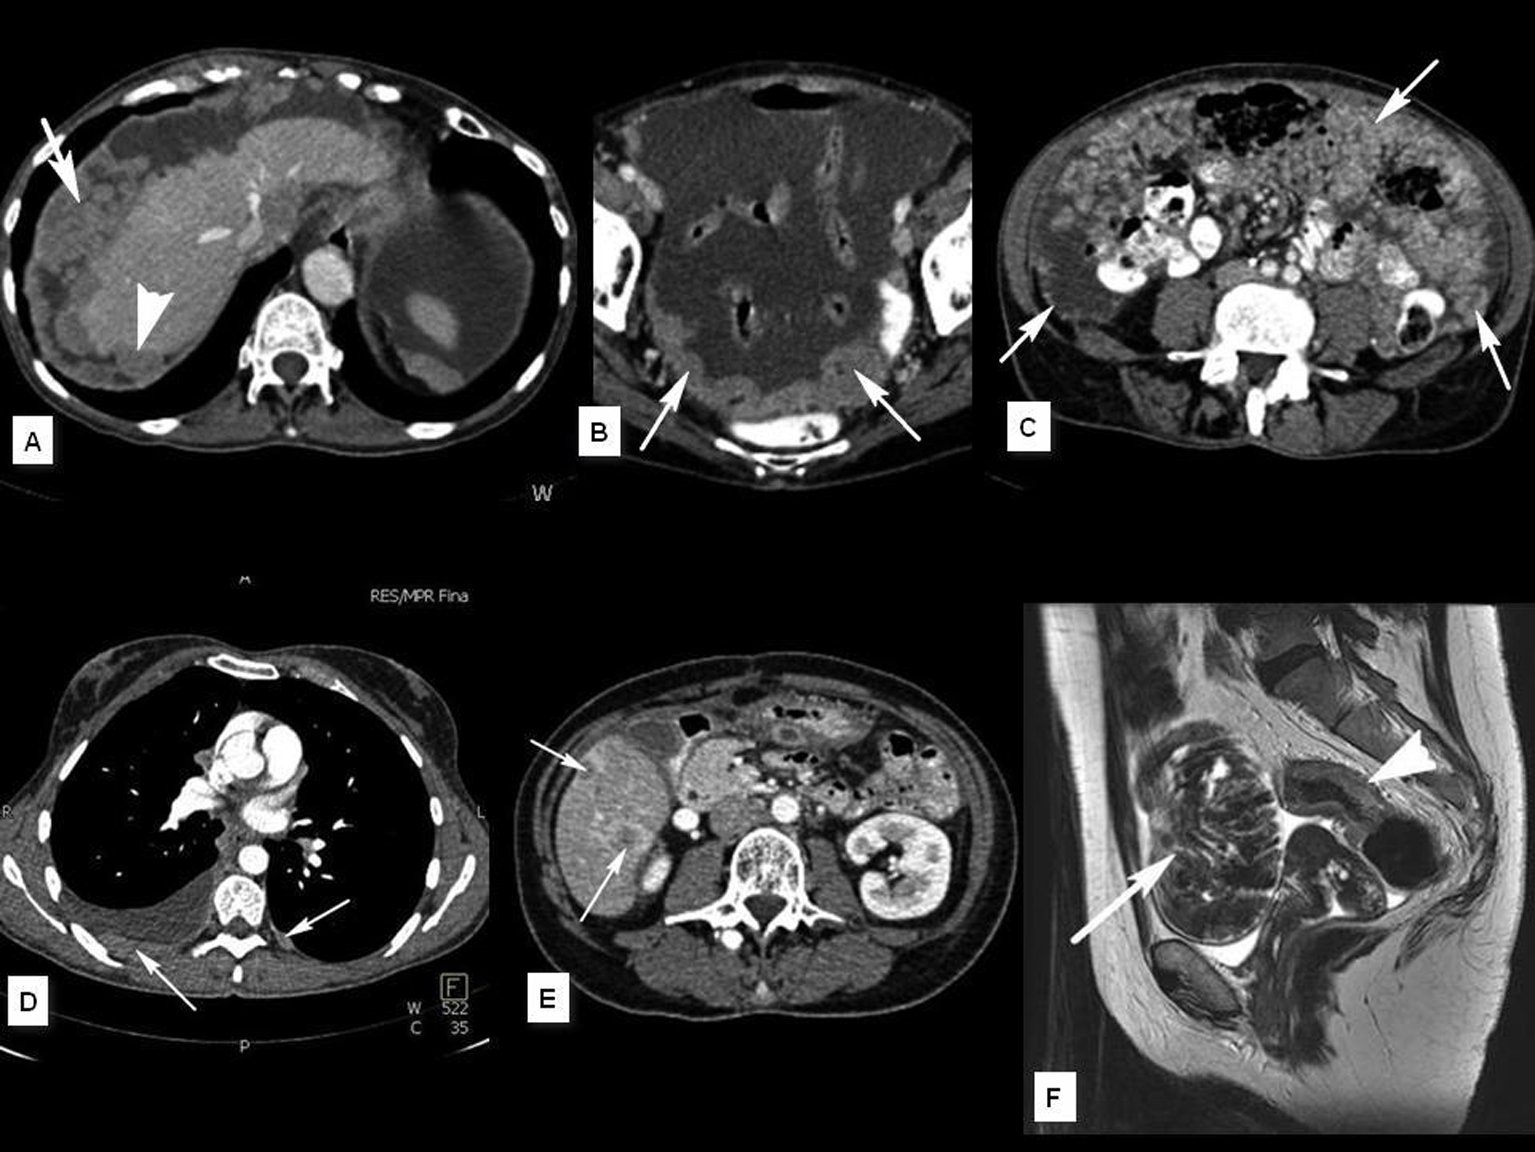

En el contexto del abordaje multidisciplinar para el diagnóstico y tratamiento del cáncer de ovario, la aportación del radiólogo incluye cuatro puntos fundamentales que son: identificación de la lesión, caracterización, estudio de extensión y valoración evolutiva. En el presente trabajo se describen los hallazgos y claves diagnósticas en TCMD (Tomografía Computarizada multidetector) y RM (Resonancia Magnética), la aportación e indicación de otras tecnologías como el PET (Tomografía por Emisión de Positrones) y se esbozan las técnicas emergentes basadas en imagen funcional (estudios dinámicos con contraste en RM y estudios de difusión por RM).Descargas